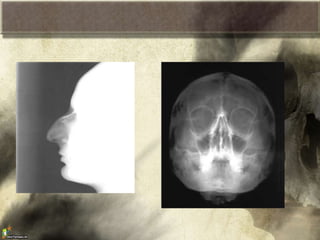

Huesos de la cabeza

Boveda craneana

Nasales

Lagrimales

Cigomáticos

Maxilar superior

Palatinos

Vómer

Cornete inferior.

(el maxilar inferior,

no se considera parte del macizo facial )

Macizo facial

Huesos de lacabeza Boveda craneana

Nasales Lagrimales Cigomáticos Maxilar superior Palatinos Vómer Cornete inferior. (elmaxilar inferior, no se considera parte del macizo facial ) Huesos de la cabeza Macizo facial